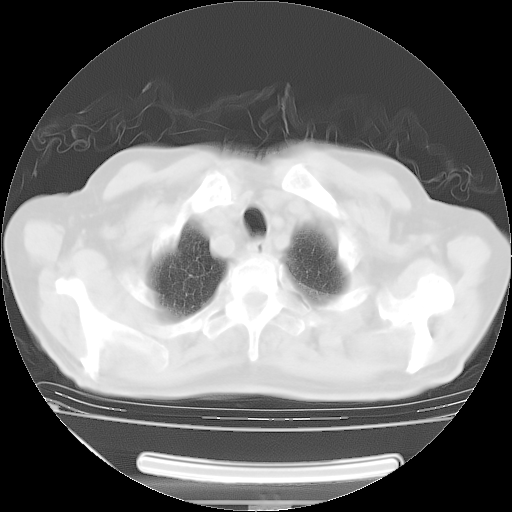

今天复查肺部CT,发现双肺广泛磨玻璃样改变。所以我把3月19日和5月9日相隔50天的肺部CT上传。请大家会诊。

2009年3月19日肺部CT片。

2009年3月19日肺部CT

5月9日肺部CT(在4月27日齐鲁医院肺部CT描述部分肺组织磨玻璃样改变,12天后肺组织广泛磨玻璃样改变)

大致读了系列胸部CT:纵隔窗无明显异常,肺窗:从4、27至今:主要是双肺中下野外带可见毛玻璃样改变,目前处于急性肺泡炎阶段,至于原因考虑1、结替组织或胶原血管性疾病所致?2、恶性疾病如恶组在肺部所致的表现或细支气管肺泡癌?3、药物或其它原因如肺蛋白沉着症所致肺泡炎目前不太可能?总之,明天就去请我院的呼吸科、感染科、血液科和临免专家会诊哈。